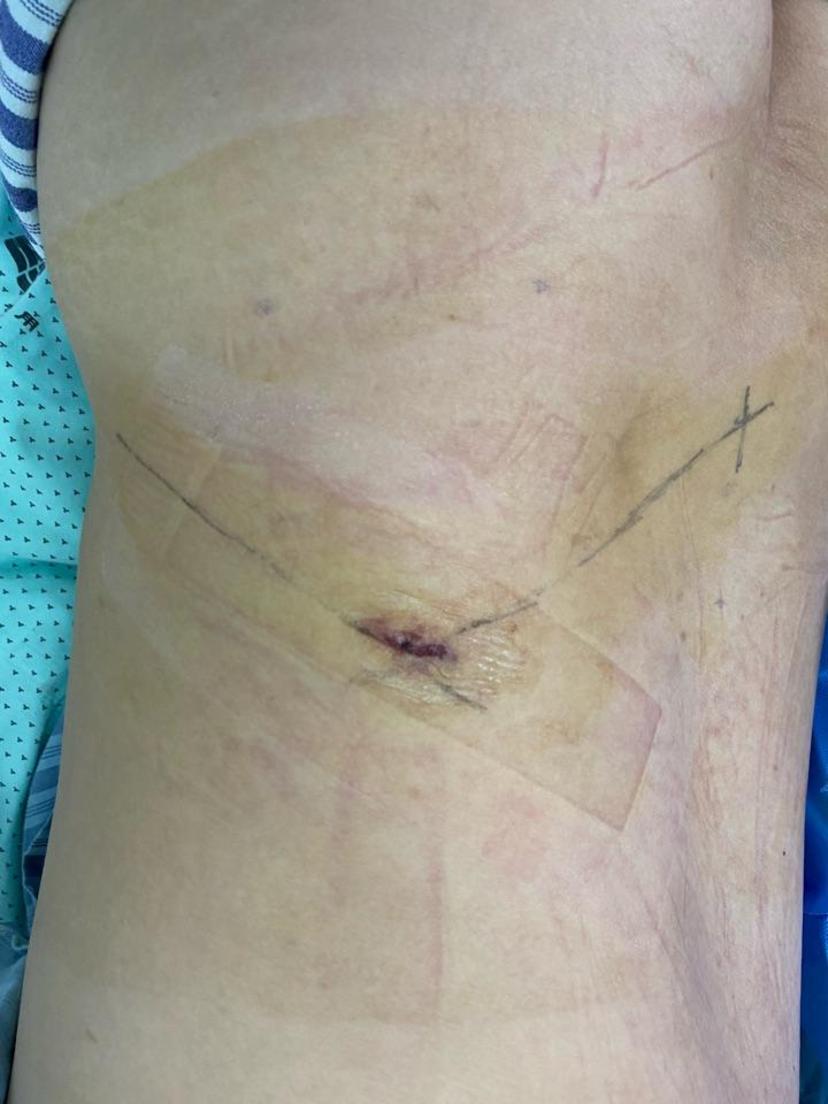

腰5-骶1巨大椎间盘突出、多日卧床行走困难,微创后第二天正常行走,总共住院三晚上!腰5-骶1巨大椎间盘突出右侧神经严重受压取出的压迫物术后右腿痛麻消失,可正常抬腿手术当天切口情况